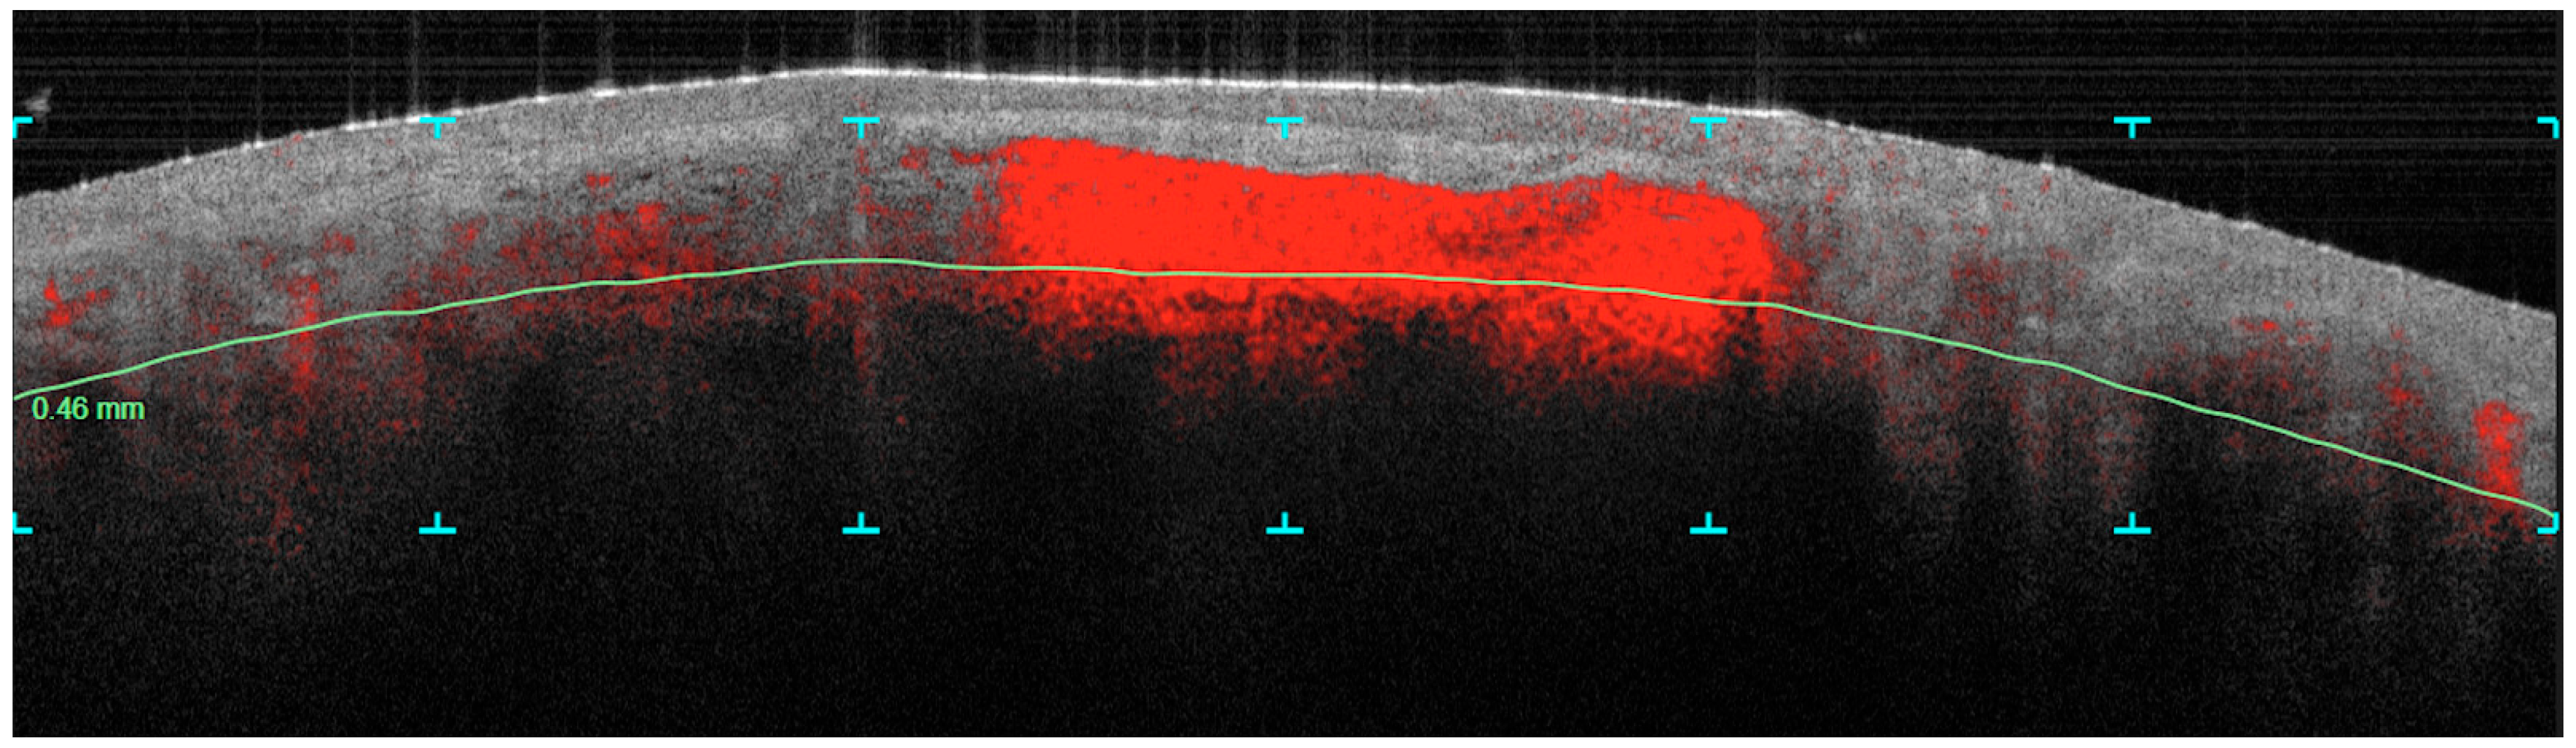

Dynamic OCT Data Analysis

- Vascular density

- Collagen density

3.1. Vascular Density Changes

- The Vascular Density at 300 µm and 500 µm shows a notable decrease in mean values from pre-treatment to post-treatment, with the p-values (1.03 × 10–141.03 × 10−14 and 1.35 × 10–151.35 × 10−15, respectively) indicating this reduction is statistically significant.